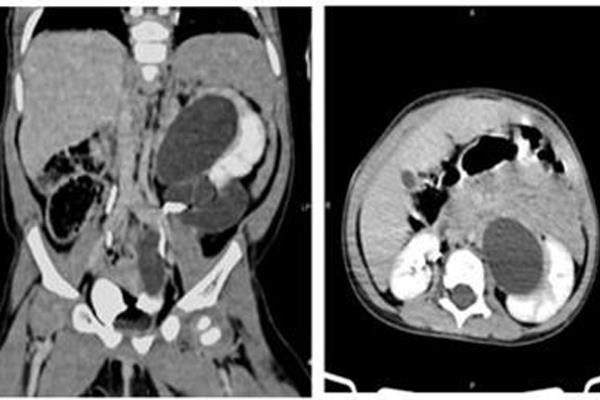

Hình ảnh 3 quả thận nhìn rõ sau khi chụp cắt lớp vi tính.

BS Triệu Mạnh Toàn, Phó khoa Ngoại nhi tổng hợp cho biết, bệnh nhi bị giãn đài bể thận trái, có 2 thận trái với 2 hệ thống đài bể thận và niệu quản riêng biệt, đơn vị thận phụ bên trái (đơn vị thận trên) ứ nước do sa lồi niệu quản vào lòng bàng quang, còn chức năng. Thận dưới trái hình thái và chức năng bình thường.